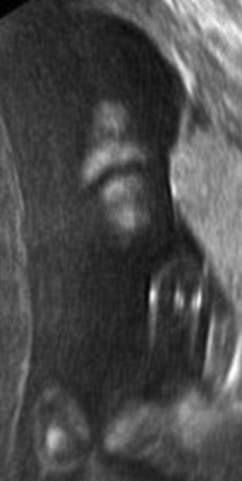

▼这个宝宝则在打自己的脸,他的动作从超音波照片中看得一清二楚。